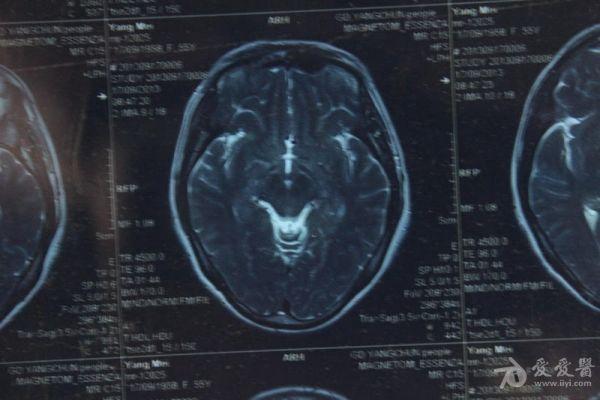

脑部占位病变CT,MRI图片,请帮忙诊断

最近感图样,无其它脑病病史

磁共振没有平扫,增强矢状位没找到病灶。像脑膜瘤。

图片不是很清楚,应该是脑膜瘤!